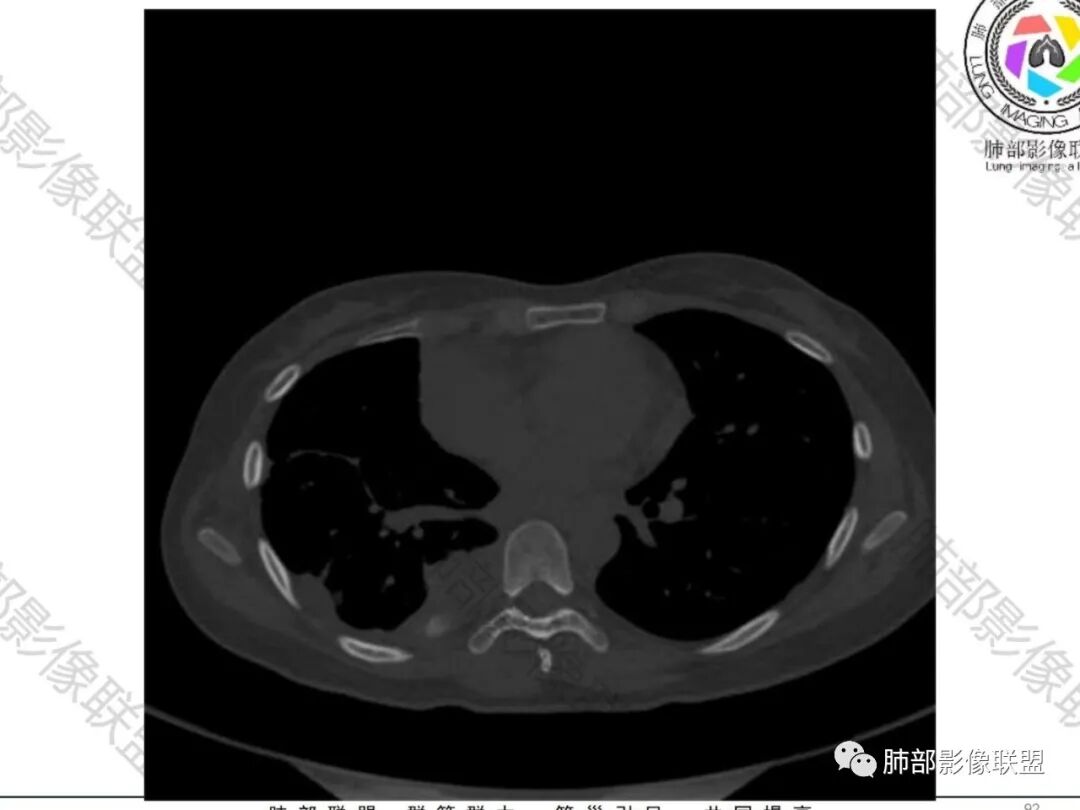

这个骨窗很有价值

价值就在于这个密度

骨质破坏,但是密度增高

你对比一下髓腔

它这个髓腔密度不对,皮质也欠连续,还是以骨头为主

南边:那就是说这个肋骨是自身的病变,有成骨性骨质破坏

肋骨伴随有溶骨性/成骨性骨质破坏,常规还是要警惕恶性